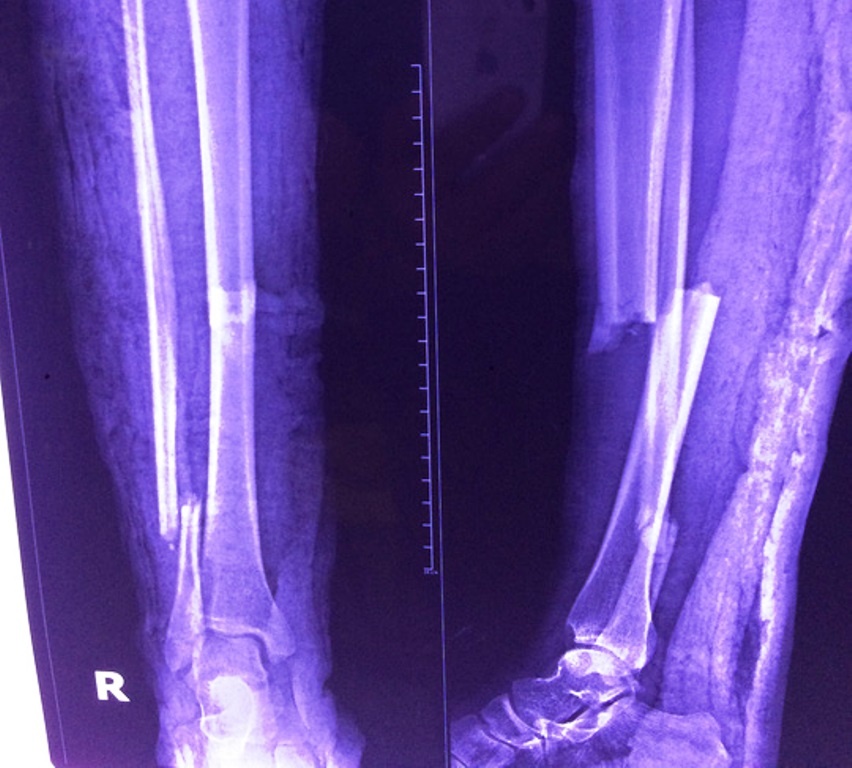

Người phụ nữ bị gãy xương cẳng chân phải thành hai đoạn, trong khi lại mắc bệnh tim bẩm sinh nặng (Fallot) nên bệnh viện từ chối mổ.